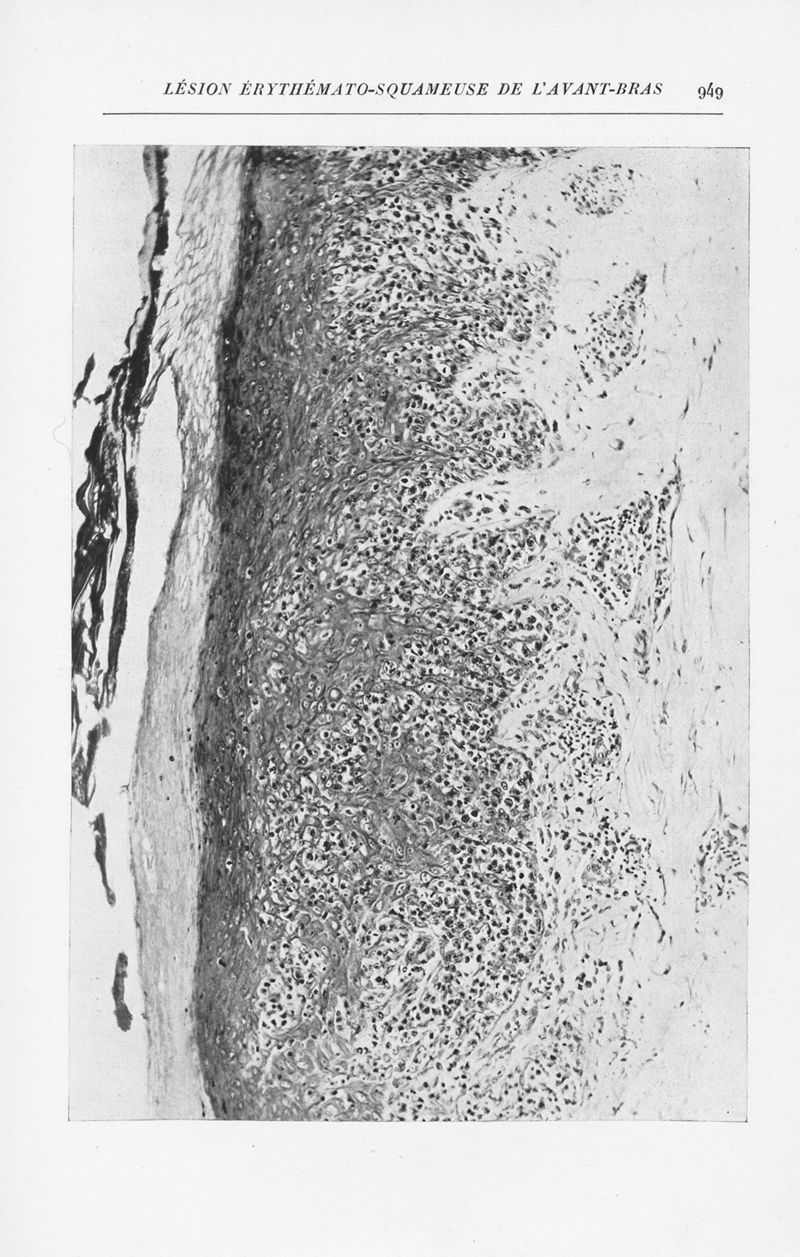

Annales de dermatologie et de syphiligraphie

7ème série, tome X. - Paris : Masson, 1939-1940.